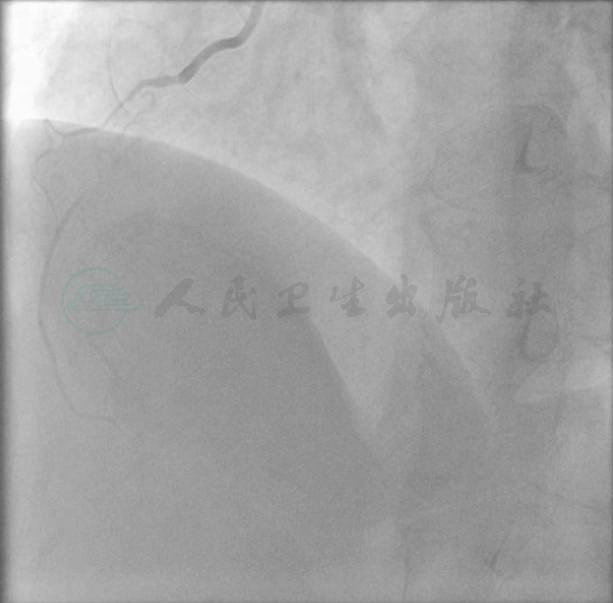

选择右侧桡动脉径路,6F 动脉鞘。造影显示:左主干未见异常,前降支中段偏心狭窄80%,回旋支中段狭窄70%,远段狭窄90%;右冠中段完全闭塞。左冠向右冠远端发出侧支循环(图1~图3)。

图1 左冠造影图(肝位)